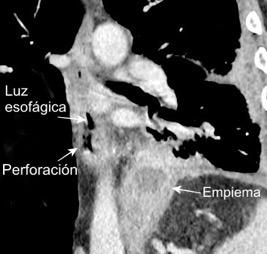

Marzo 2014: Perforación longitudinal distal secundaria a episodio de vómito (síndrome de Boerhaave). Derrame pleural izdo. que evoluciona a empiema.

Wang C-T et al. Tension hydropneumothorax in a Boerhaave syndrome patient: A case report . World J Emerg Med, 2021. Katabathina V et al. Nonvascular, nontraumatic mediastinal emergencies in adults:a comprehensive review of imaging findings. Radiographics. 2011.